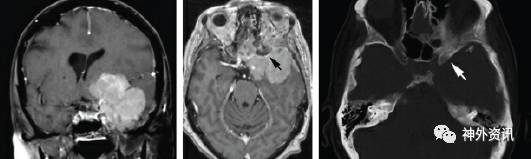

图2. 蝶骨嵴内侧型脑膜瘤,肿瘤浸润引起前床突骨质增生的MR影像(黑色箭头)和CT影像(白色箭头)。